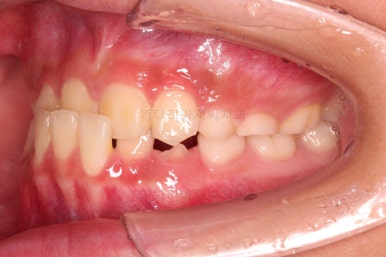

CASE 2.

나이 : 8세

총 치료기간 : 2주(2달 아님, 2주 맞음)

마찬가지로 얼굴모습 부터 분석해요.

골격에 문제가 있는 진짜 주걱턱은 아니라고 판단이 되었어요.

대신 앞니가 거꾸로 물려있어 웃는 모습부터 드러나는 치열의 모습까지 부자연스러운 모습인데요.

이번 환자분도 치료가 굉장히 빨리 끝났어요.

2주만에 해결!

바로 부산어린이교정 전후사진 비교해 볼게요.

단, 2주만에 문제시 되는 딱 한 개의 치아에만 포커스를 맞춰 해당 치아 반대교합만 개선해준 매우 훌륭한 치료였습니다.